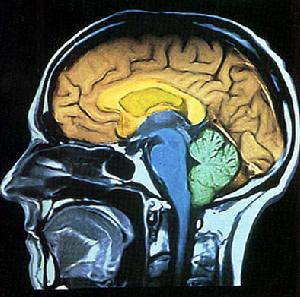

幻覺記憶介紹 很多科學家因幻覺記憶與過去生活體驗、直覺(ESP)和不尋常誘因的經常關聯性而將其完全忽略。這些關聯給幻覺記憶的研究帶來了一點“恥辱”。最近,研究人員將其中一些關聯擱置一旁,開始研究大腦影像技術。他們將幻覺記憶牢固地鎖定在記憶研究的範圍內,希望發現有關記憶是如何形成、存儲和檢索的更多信息。

自此,他們確定中間顳葉存在於我們的意識記憶中。中間顳葉中包含海馬旁回、頂葉皮層和扁桃體。史丹福大學的約翰·D·E· 加布里埃利在1997年發現海馬狀突起能使我們有意識地回憶起事件。他還發現海馬旁回能讓我們確定什麼是熟悉的、什麼是不熟悉的(無需實際地檢索特定記憶即可實現)。